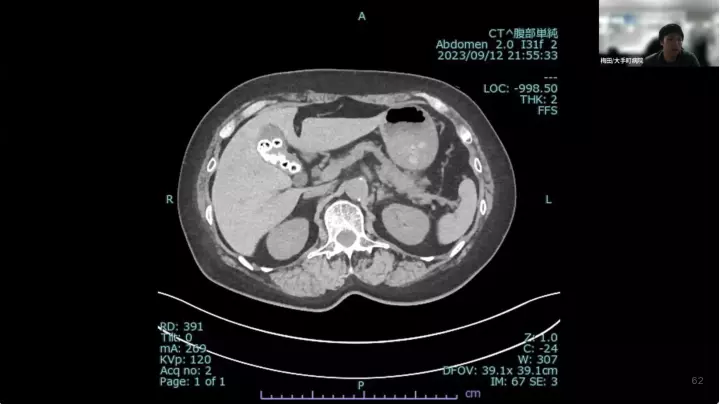

外科医目線の~急性胆嚢炎~治療編